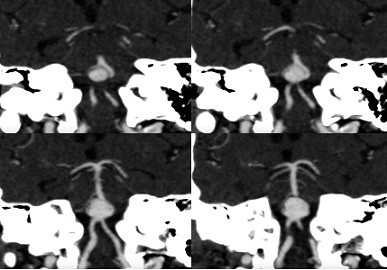

CT revealed a large saccular aneurysm of 13 x 16 mm, with a wide neck (05 mm), implanted on an asymmetric fenestration of the vertebrobasilar junction, without any sign of complication (Figures 1-3).

Figure 2: Oblique coronal reconstructions with MIP (Maximum Intensity Projection) allow visualization of the asymmetric fenestration of the basilar artery at its origin, with a right branch (blue arrow) and a dominant left branch (green arrow), surrounding the aneurysmal sac (red arrows).